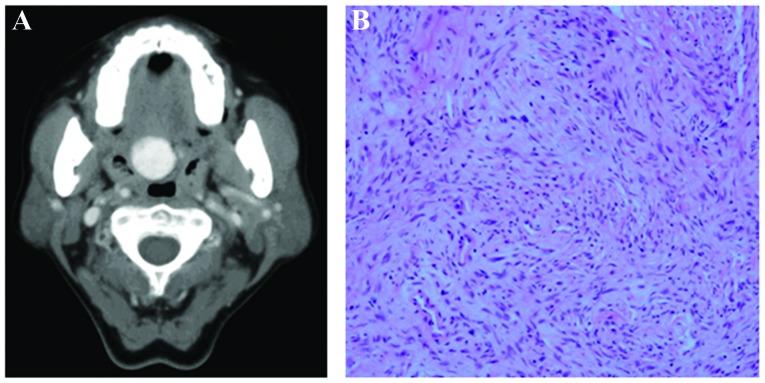

Solitary fibrous tumors (SFTs) are a unique group of mesenchymal neoplasms of fibroblastic or myofibroblastic origin and are extremely rare in the oral cavity. The present study reported two additional cases of SFTs in the soft palate, along with the computed tomography characteristics, which demonstrated well-circumscribed soft tissue lesions with marked and homogenous enhancement. Following wide resection, one of the cases showed certain malignant pathological characteristics, including infiltration of mucinous gland, hypercellularity, nuclear atypia and weak positive staining for S-100. In our experience, SFTs should be considered as a differential diagnosis when a well-circumscribed and solid mass in the soft palate is identified.